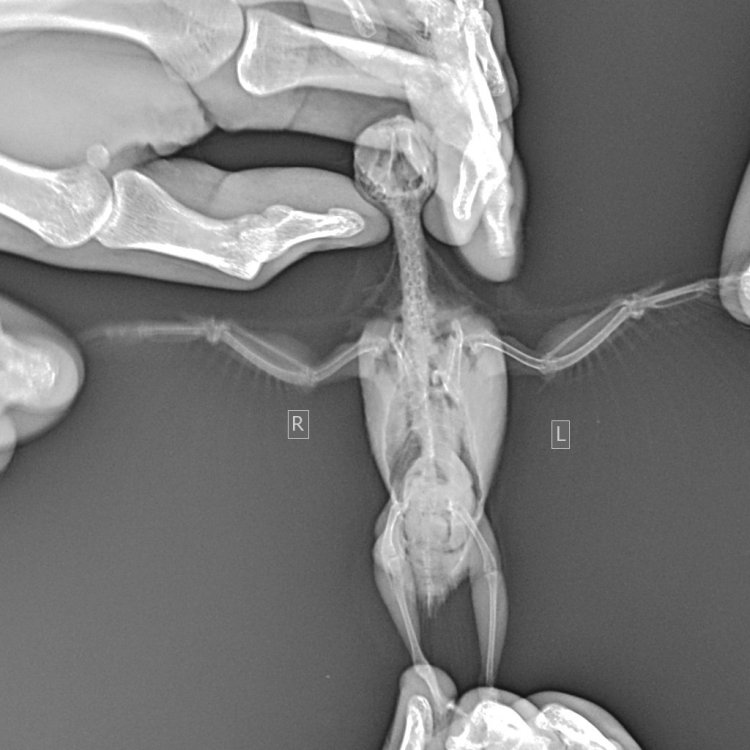

Здравствуйте. Помогите, пожалуйста, разобраться. Волнистый попугай, девочка, 3 года 5 месяцев. Лечили мегабактериоз, на вчерашней микроскопии ни одной мегабактерии, однако рвота и непереваренные зерна в помете остаются. Сделали рентген, орнитологи в замешательстве, у каждого свое отличное мнение по поводу преджелудка , печени и новообразовании в лёгких. В помете также нашли много пыльцы, однако возможно , что это глисты. Снова не понятно. Помогите , пожалуйста, разобраться с рентгеном и микроскопией. Фото прикладываю.